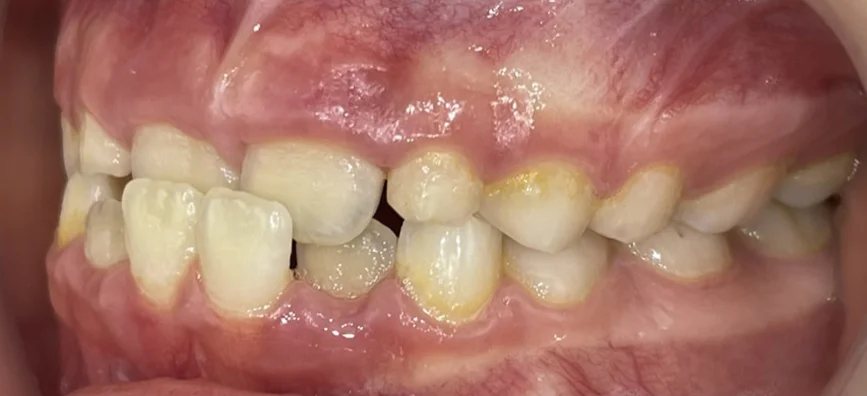

Търсейки детски ортодонт, пациентът дойде с основни оплаквания – “Долните зъби са пред горните” Кръстосаната захапка във фронта, затруднение при отхапване, нарушена естетика.

Кръстосана захапка във фронталния участък

Компресия на челюстите

Струпване и липса на място за пробива на постоянните зъби

Пациентката идва на първо посещение още когато е на 6- годишна възраст, наблюдава се пробив на централни долни резци зад млечните резци. Направена е екстракция на млечни резци 81 и 71.